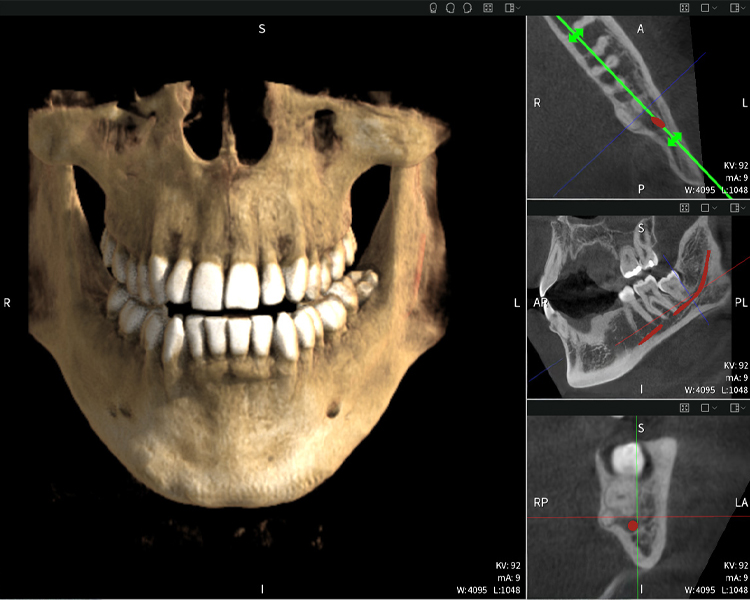

Nachstehend finden Sie einen Fall von Dr. med. dent. Oliver A. Centrella, in dem die CBCT-Aufnahmen mit Seethrough Max entscheidende Informationen zur komplexen Anatomie sowie zur kritischen Beziehung zwischen den Weisheitszähnen und dem Nervus alveolaris inferior lieferten. Bei diesem Fall besteht eine Indikation zur chirurgischen Entfernung der Weisheitszähne.

Abbildungen b–d zeigen verschiedene Ansichten einer 3D-Rekonstruktion des Unterkiefers und bieten eine umfassende Übersicht über die Anatomie des Unterkiefers, die Lage der Nerven im Verhältnis zu den Zähnen und ermöglichen die Beurteilung der Zahnsymmetrie und Ausrichtung.

Abbildung d zeigt den bereits vorbehandelte Zahn 48, dessen Krone entfernt wurde und dessen Wurzeln nahe am Nerv belassen wurden, was das hohe Risiko einer Nervenschädigung verdeutlicht.